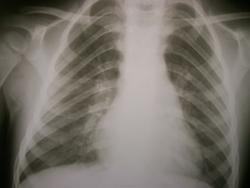

Первые 2 снимка сегодня, вторые 2 майские.

До этого с 21.05 по 28.05 лежал в детском отделении и по снимкам я ставила нижнедолевую пневмонию справа.

Самостоятельно родители свозили реьенка в область. Рентгенолог областной детской больницы описала, что инфильтрации нет, а есть сгущение легочного рисунка в нижней доле справа. И в заключении выставила " признаки обструктивного синдрома".

А динамика-то положительная.Среднедолевая,наверное,была.

На прямом снимке справа сохраняется расширение корня, "замазанность" кардио-диафрагмального угла. R-динамику продолжить, учитывая анамнез.